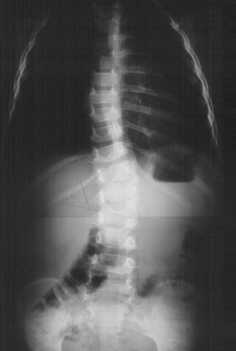

Ci troviamo di fronte a una scoliosi a esordio molto precoce. Il problema è, naturalmente, quello di stabilire un programma di controllo o di intervento. Viene consigliata innanzitutto l'esecuzione di un radiogramma del rachide in toto: si evidenzia così la presenza di una scoliosi cosiddetta "congenita", dovuta alla presenza di un emispondilo a livello di L1.

La valutazione in gradi Cobb della curva corrisponde a 20°. Un angolo di Cobb (vedi Figura1) di 20° è al limite della gravità che richiede un trattamento. Ricordiamo che l'angolo di Cobb si ottiene unendo le rette che passano per i piatti delle vertebre più inclinate, rispettivamente in alto e in basso.